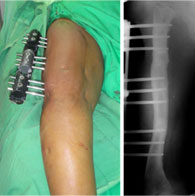

The appearance in the frontal plane once the varus angulations are corrected and the LRS (Limb Reconstruction System) assembly is completed.

The picture on the right is the x-ray appearance with the corrected bony axis.

The appearance in the sagittal plane once the flexion deformity is corrected and the LRS (Limb Reconstruction System) assembly is completed.

Also seen are the small incisions (red arrows) through which the percutaneous osteotomies were performed.